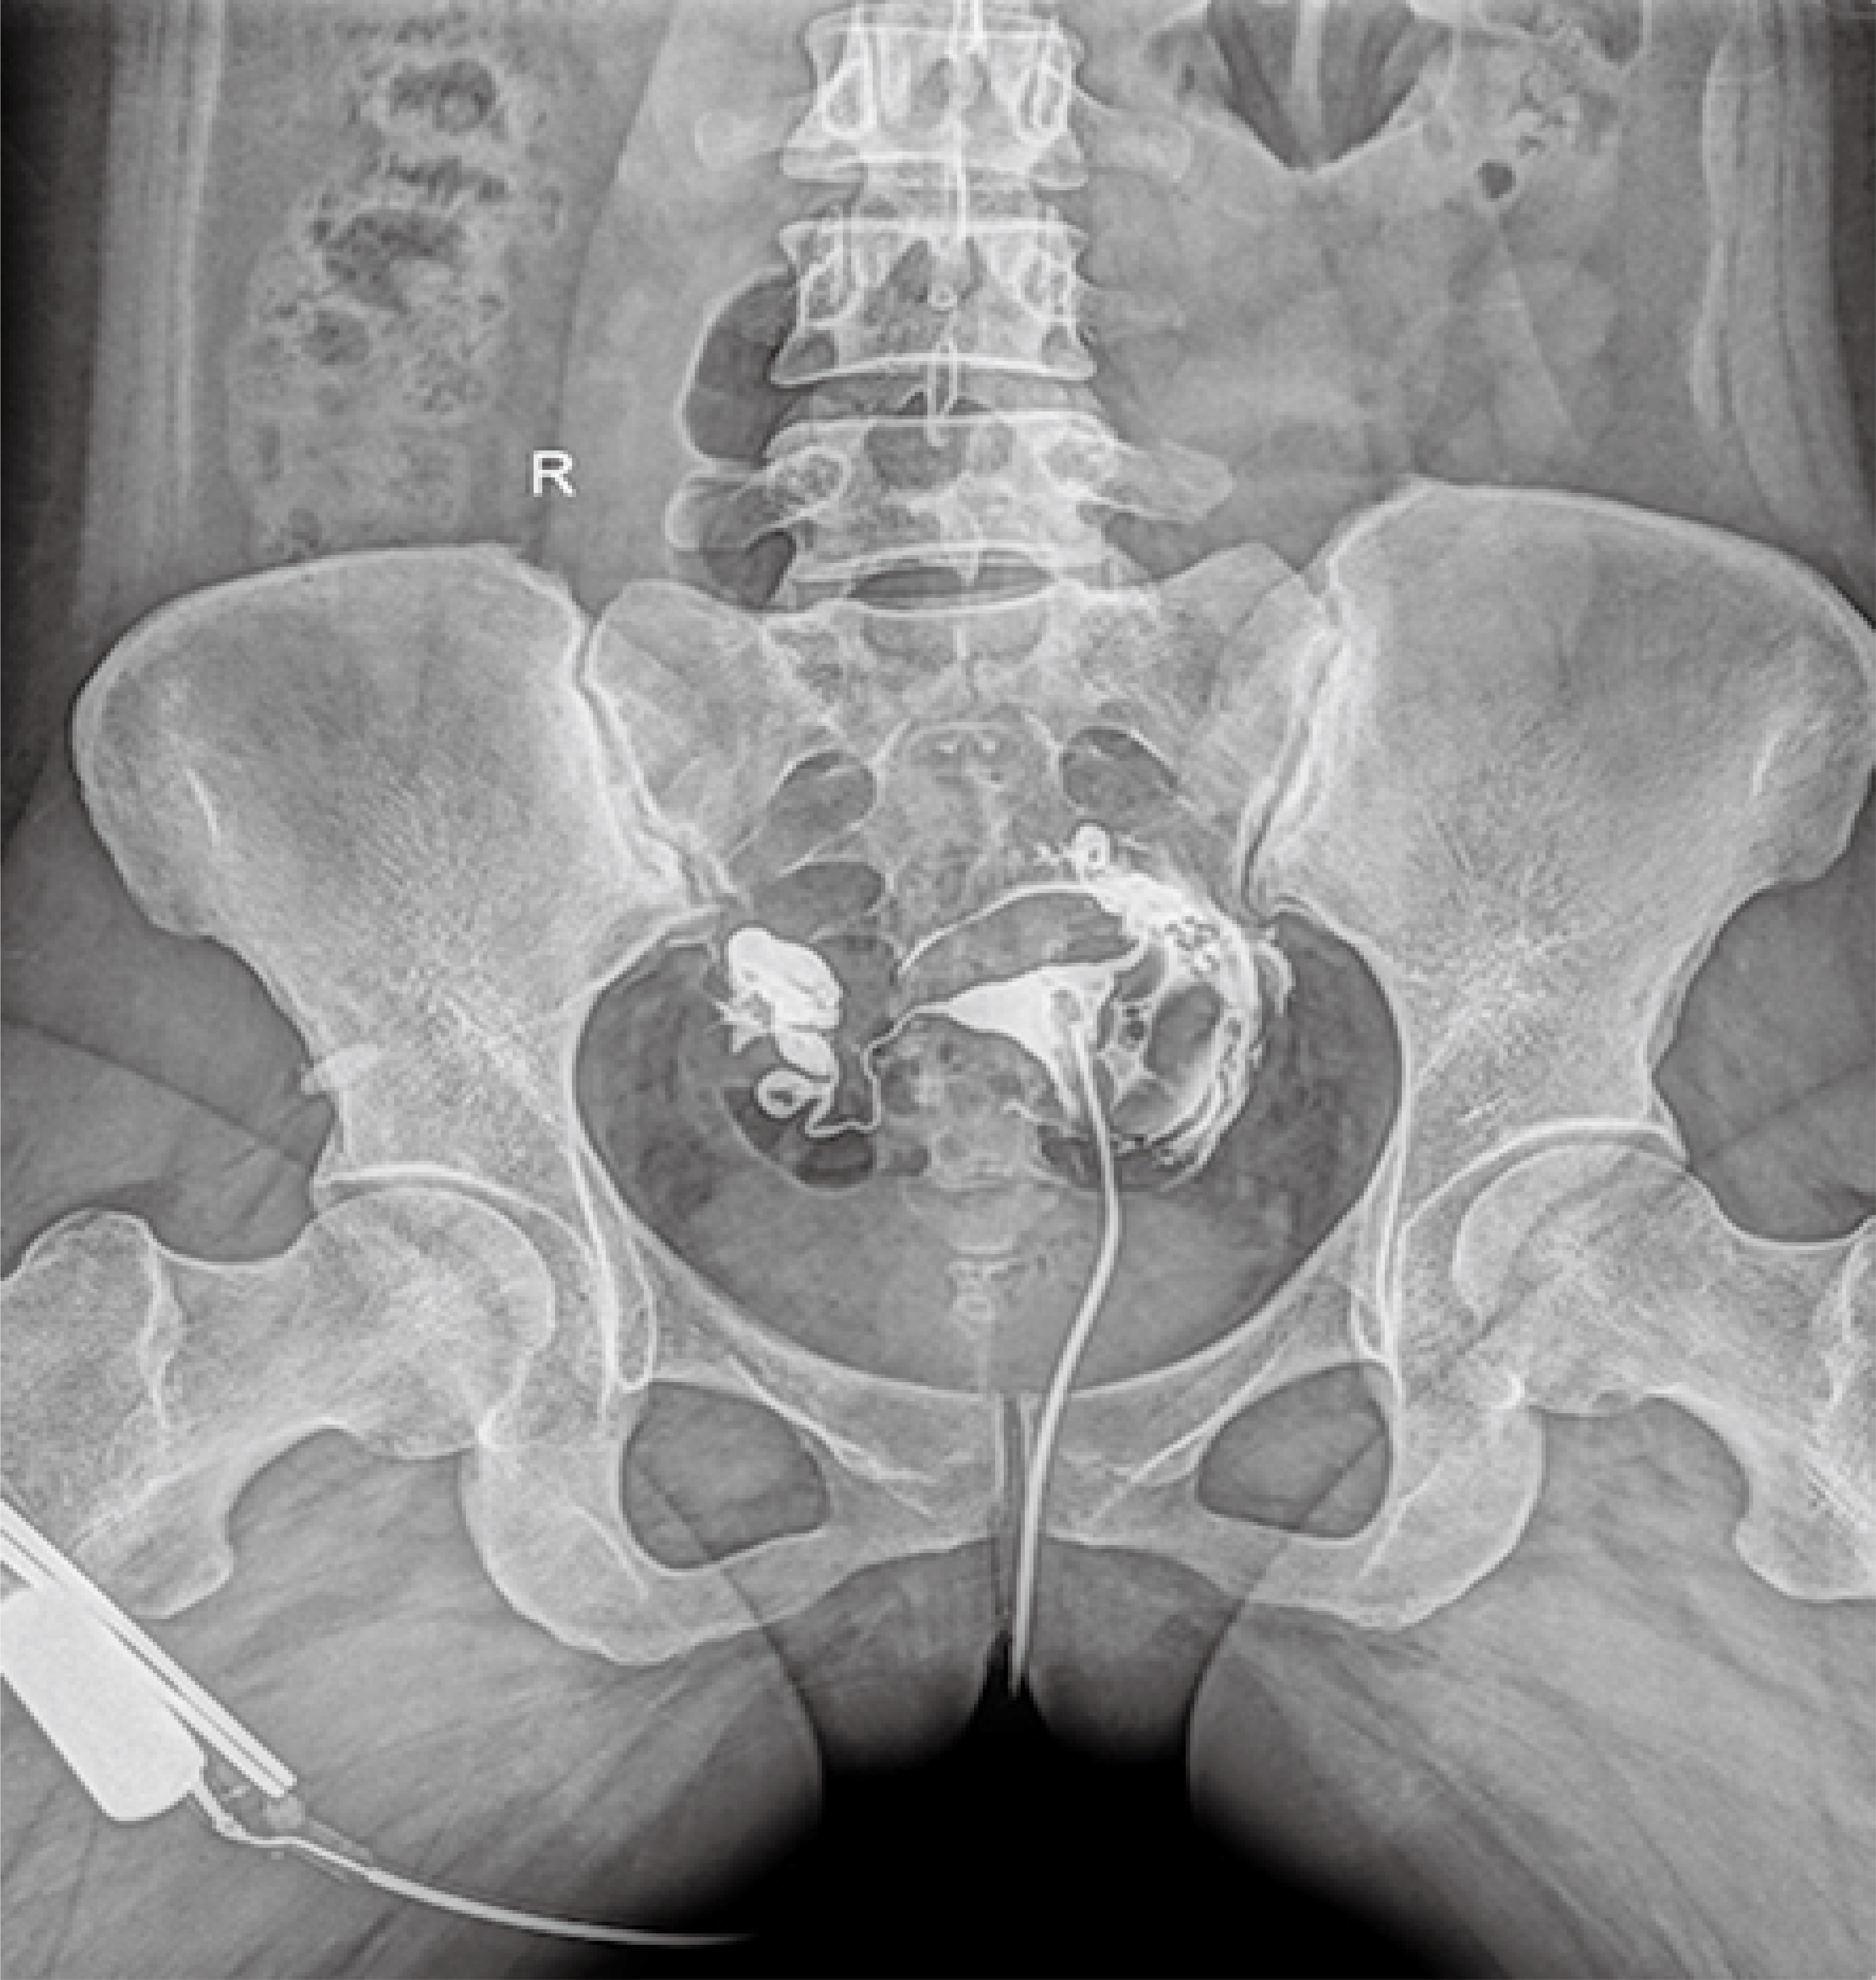

普利德醫療自主研發(fā)的新一代數字化X線(xiàn)透視攝影系統,可應用于DR攝影、數字透視、數字造影以及可視化精準DR拍片等多種臨床X線(xiàn)檢查領(lǐng)域。

● 17*17英寸的超高清像素動(dòng)態(tài)平板探測器,更大的視野范圍,無(wú)需移動(dòng)即可觀(guān)察整個(gè)動(dòng)態(tài)過(guò)程,避免拖尾、噪聲對圖像的影響;

● 高效動(dòng)態(tài)平板技術(shù),圖像不會(huì )有幾何畸變,提供高分辨率和精確的圖像,為醫生臨床診斷提供精準依據;

● 最高幀速可達30幀/秒,動(dòng)態(tài)采集清晰流暢,避免漏診、誤診情況的發(fā)生;

● 在可視過(guò)程或回放過(guò)程中,如發(fā)現疑似病灶,可進(jìn)行毫秒級高清點(diǎn)片,隨時(shí)抓取單幀圖像,精準捕抓病灶。